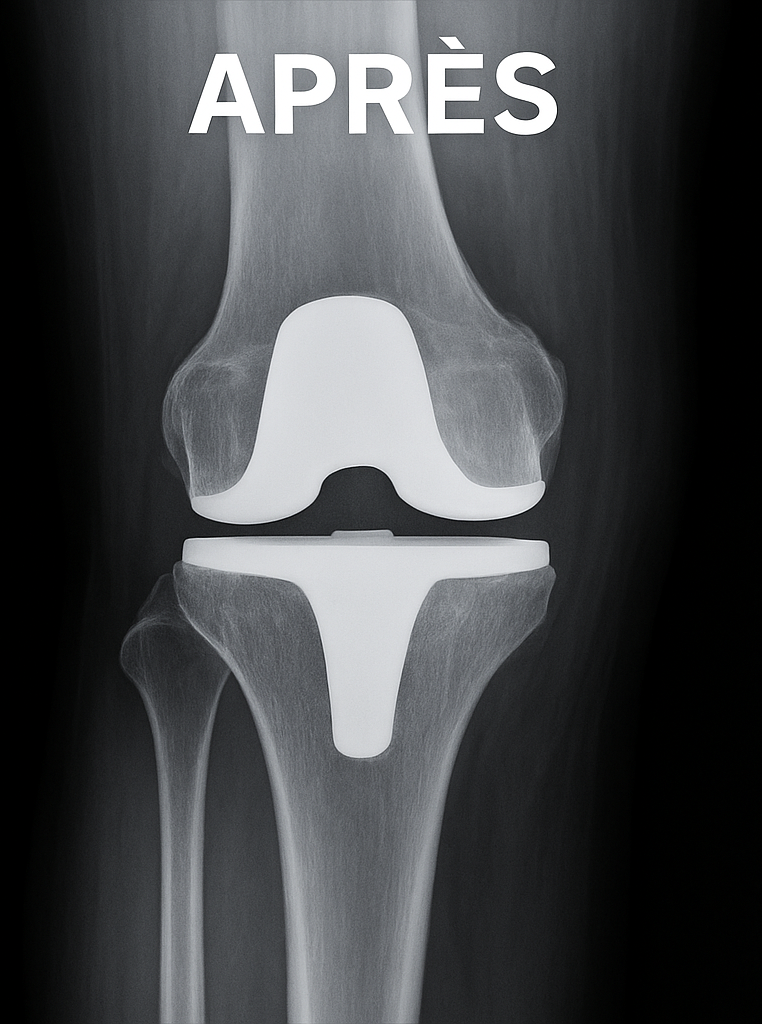

Illustration radiologique

Prothèse du genou